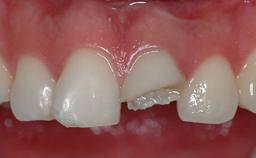

An 80-year-old female patient was referred to clinic for rehabilitation of her dentition. The patient’s medical history revealed no significant findings that would preclude routine dental and oral surgical procedures. She reported no drug allergies and was currently taking no prescription medications.

Her chief complaint was her inability to masticate efficiently due to the recent loss of her mandibular second premolars and first molars bilaterally. She expressed a desire for fixed prostheses in the shortest possible time due to her advanced age, requesting that replacement teeth should look as natural as possible. She was otherwise comfortable and not experiencing any symptoms from her teeth.

Prosthesis Type FDP

Loading Protocol Conventional or early

Retention Screw-retained, with 2 splinted implants Screw-retained, with 2 splinted implants